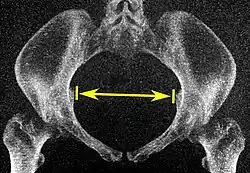

Tomografias computadorizadas de baixa dose em 3D podem ser usadas para estimar os principais parâmetros da pelvimetria:[4]

| Abertura superior da pelve | Diâmetro transverso da abertura superior |

|

Plano coronal |

As linhas iliopectíneas, na maior distância transversa. | 13 a 14,5 cm.[4] |